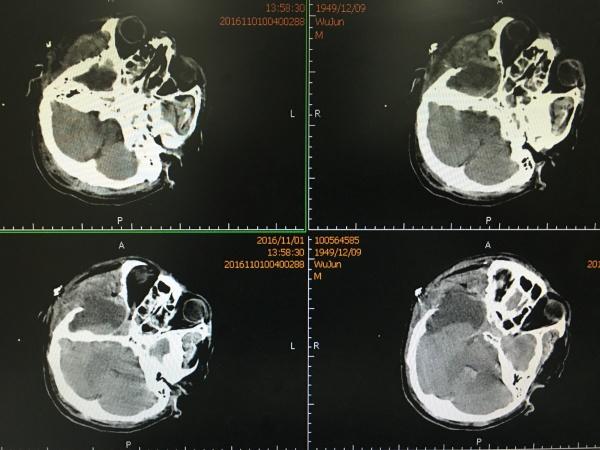

见MCA供血区大面积梗塞,查凝血无明显异常,予以改善微循环、扩容等对症治疗,1周后再次复查CT:

CT所见MCA供血区梗塞明显好转,骨窗处见硬膜下积液,此时患者评分改善,刺痛可睁眼,有摸索动作。